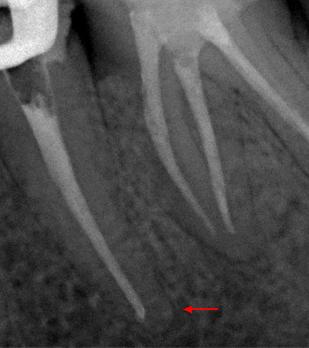

Пациент 45 лет направлен лечащим доктором на перелечивание 35 зуба.

Со слов пациента эндодонтическое лечение проводилось три года назад.

На рентгенологических снимках представлена картина до лечения, диагностический снимок и конечный результат.